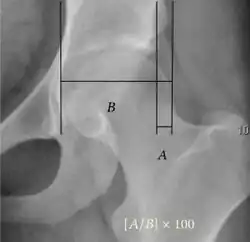

- Reimer's migration index (MI), also called the femoral extrusion index,[3] is calculated if hip dysplasia is detected. It can be used to indicate hip dislocation. It is the horizontal distance (parallel to the Hilgenreiner Line) between the Perkin line and the lateral border of the ossification center of the femoral head, divided by the horizontal width of the ossification center. The migration index is normally less than 33% by most sources,[9] but 25% and 30% has also been suggested.[10]

| Reimer's migration index[9] |

|

The percentage of the femoral head that lies outside of the acetabular roof. It is also called the femoral extrusion index. | <25% |